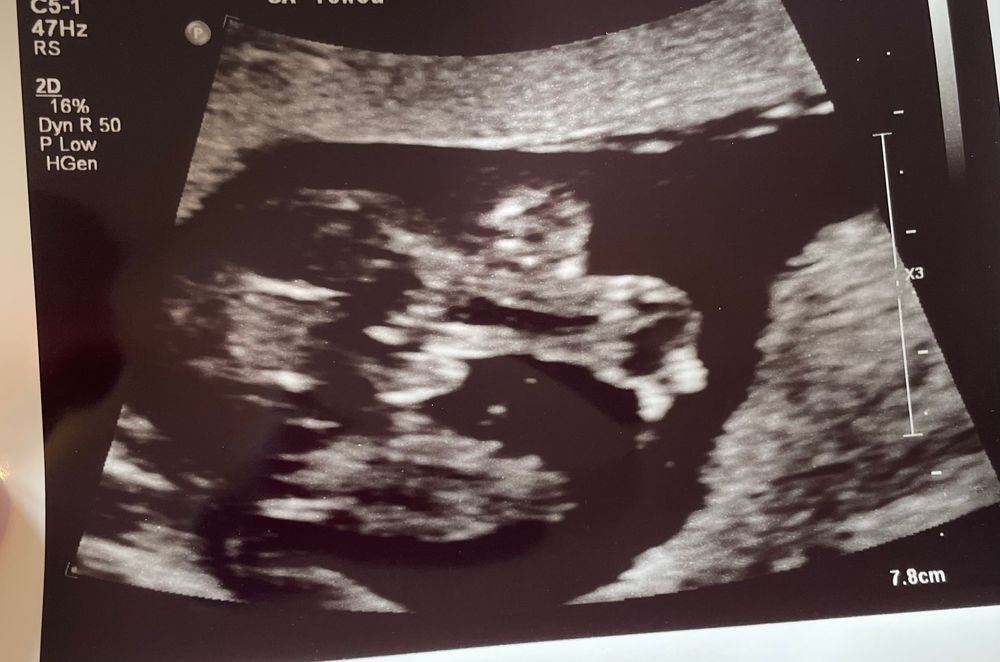

Была на узи 16 недель

Врач сказал что 100% мальчик, но почему-то переживаю точно ли😅

Девочки кого вы видите?😅

Мальчишка же)))